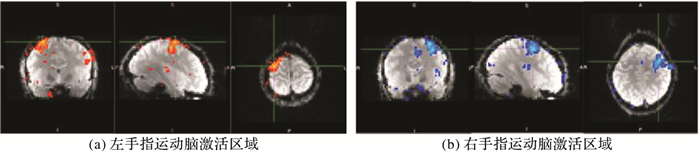

左、右手指运动任务及分别正交化后的实验结果如图 4~6所示,表 2~4分别为对应图 4~6左、右手指运动任务主要激活区域的定位。

图 4 左手指运动任务和右手指运动任务脑激活图 Figure 4 Brain activation map of left finger movement task and right finger movement task |

根据实验结果图 4可知,左手指运动任务激活区域主要对应大脑的右半部分,右手指运动激活区域主要对应大脑的左半部分。在实验过程中,左、右手指运动任务之间相互影响,当只对其中一种任务的激活区域感兴趣时,就需要消除另一种任务对它的影响,即通过正交化来消除二者之间的相关性。图 5、6中的黑色圆圈部分分别表示执行正交化后与未做正交化脑激活区域的不同。从表 2~3可以看出,将左手指运动任务关于右手指运动任务正交化后,右手指运动的激活区域与之前相比发生变化,激活体素数增多,而左手指运动的激活体素数保持不变。这是因为经过正交化后,左、右手指运动任务变成两个独立的回归量,原来由左、右手指运动共同表示的激活区域现在全部由右手指运动表示。虽然左手指运动回归量的估计参数保持不变,但它现在表示减去两者共线之后的部分,其解释发生改变。